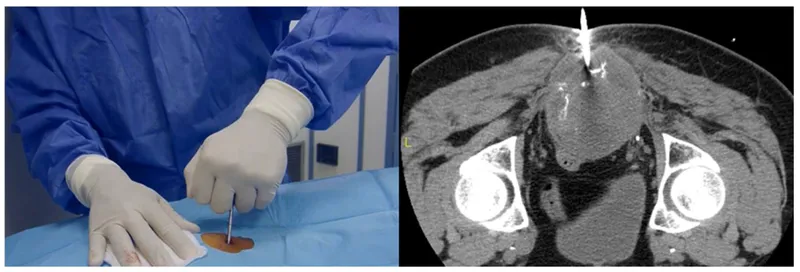

Needle Biopsy (Percutaneous):

- Pros: Minimally invasive, local anesthesia, ↓cost, ↓morbidity, outpatient. Often image-guided (USG/CT).

- Cons: ↑Sampling error risk (heterogeneous tumors). Coaxial technique ↓seeding.

- Accuracy: CNB ~90-95% with experience.